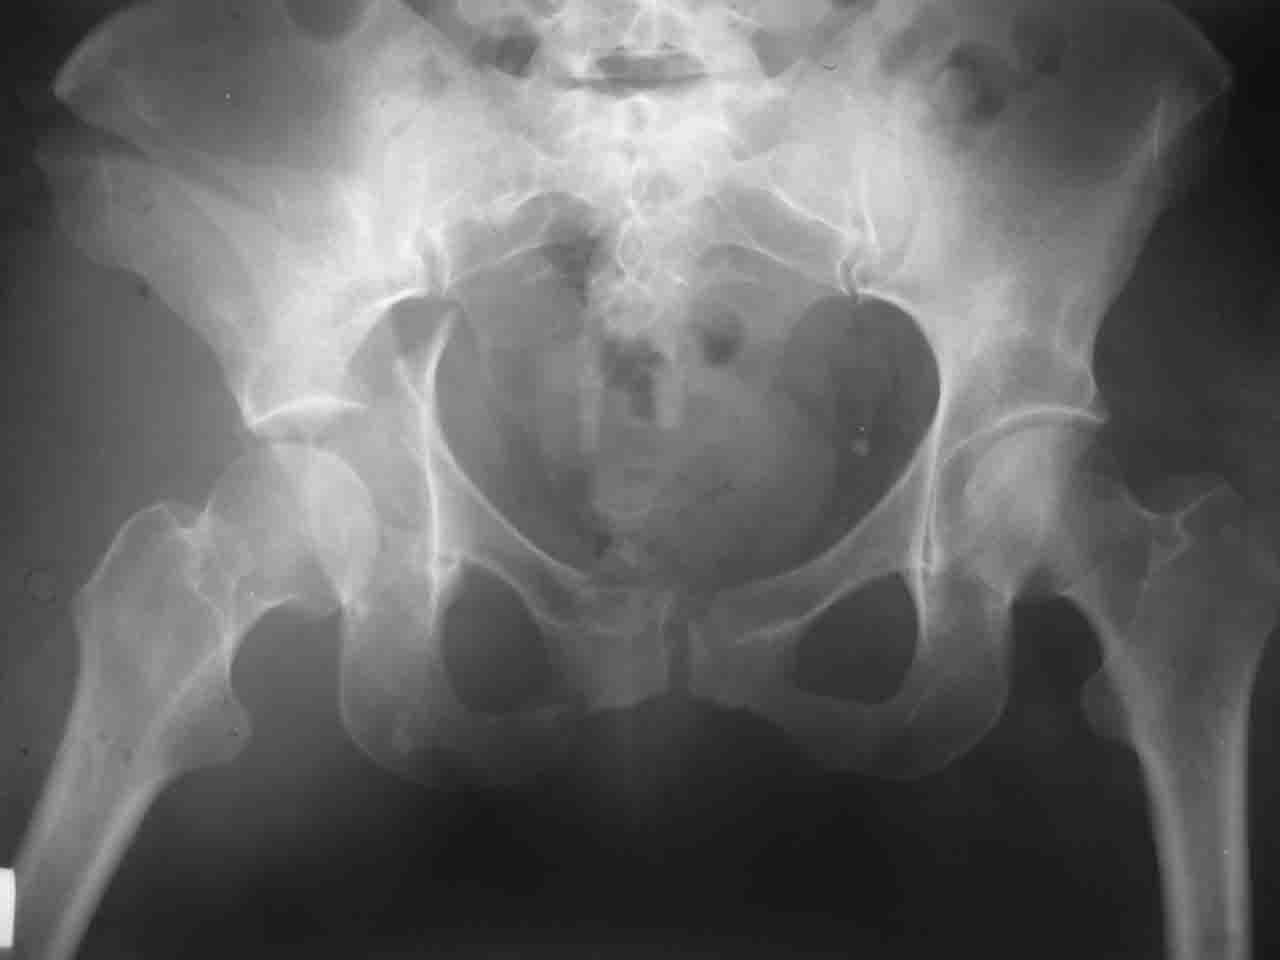

Интерес к реконструкции вертлужной впадины у меня появился довольно-таки давно, но до недавнего времени как-то не ощущалась готовность к практической реализации, а местный подход достаточно консервативен - перелом срастется,

а далее будет видно. Такую точку зрения я не разделяю, поэтому через конференции,ортофорум и свои случаи пытаюсь практически и теоретически *продвинуть* для себя тему реконструкции вертлужной впадины.

Логика подсказывает, что все-таки лучше иметь анатомически полноценную впадину, хотя ранее упоминалось состояние вторичной конгруэнтности и одно наблюдение у меня есть, когда у больного с полностью нарушенной анатомией впадины и подвывихом головки бедра кзади и кверху боли отсутствовали при относительно достаточном для стиля жизни больного объёме движений. Но это только одно наблюдение и кроме перелома впадины у этогобольного была и тяжелая ЧМТ в анамнезе. Основываясь на формулировке структуры ацетабулюм Э. Летурнеля - как перевернутой буквы Y, впадина для полноценной функции сустава должна иметь сферичность, соответствующую размеру головки бедра и если один из компонентов в дефиците, то функциональные последствия рано или поздно проявятся.

Сложностью, ассоциативностью характера перелома, я бы с радостью воспользовался мининвазивной перкутанной фиксацией винтами, но боюсь, что результат был бы ещё хуже, техникой непрямой репозиции перелома не владею, поэтому пытаясь получить анатомичную впадину приходится широко открывать, по крайней мере пока, а дальше буду пытаться уменьшать пространство...